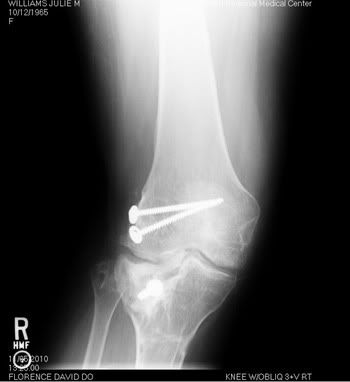

Most people don't understand why I am the way I am. I hope these x-rays give them a better idea of what I have to deal with every single day.

My right knee: